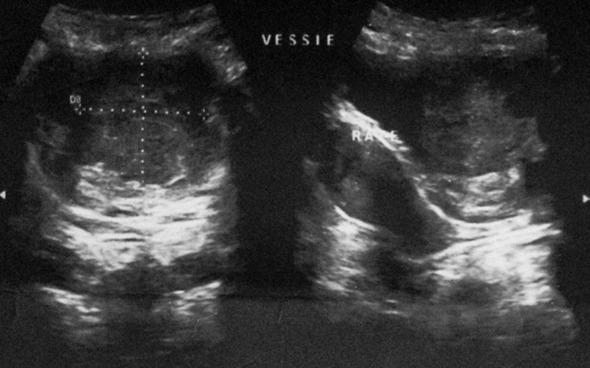

Bladder schwannomas are exceedingly rare, benign or malignant, nerve sheath tumors that are most often discovered in patients with a known diagnosis of Neurofibromatosis type 1 (NF1). A few sporadic case reports of bladder schwannoma have been published in urologic, obstetric/gynecologic, and pathologic journals. We report a case of an isolated schwannoma of the urinary bladder. To our knowledge, this represents only the sixth case of benign schwannoma of the urinary bladder in a patient without von Recklinghausen disease.

膀胱神经鞘瘤极为罕见,是一种良性或恶性的神经鞘肿瘤,最常出现在已确诊为1型神经纤维瘤病(NF1)的患者中。泌尿外科、妇产科和病理学杂志上已发表了几例膀胱神经鞘瘤的散发病例报告。我们报告一例孤立性膀胱神经鞘瘤病例。据我们所知,这是仅有的第六例在无冯雷克林霍增氏病患者中发生的膀胱良性神经鞘瘤病例。